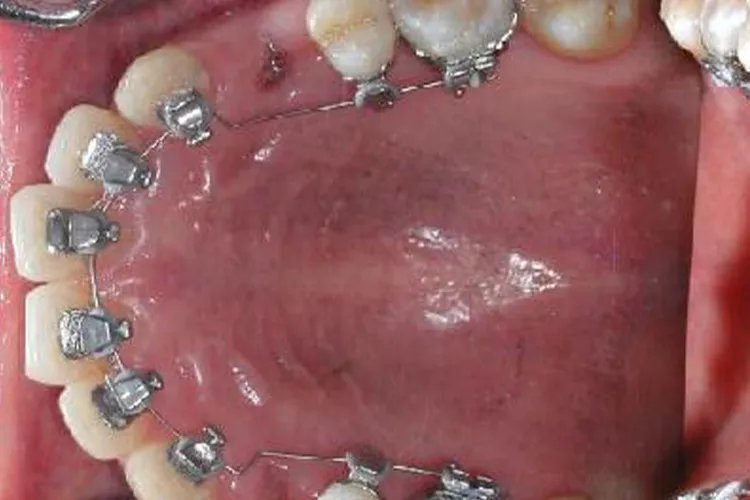

概述矫正牙齿即口腔正畸治疗,是将不整齐的牙齿排列整齐,恢复牙齿的咀嚼和美观等功能,儿童和成人都可以进行牙齿矫正。矫正牙齿需要佩戴矫正器,矫正器的种类较多,包括传统金属托槽矫正器、自锁托槽矫正器、半隐形矫正器、全隐形矫正器等。矫正器类型传统金属托槽矫正器传统金属托槽矫正器用专用的黏结剂把金属或其他材料固定在牙齿表面,用于容纳固定正畸钢丝,传递矫正力到牙齿,从而法到矫正牙齿的目的。特点是安全健康,技术成熟,降低拔牙率,可将复诊时间缩短为8~12周,且小巧,能够有效减少口腔不适感。自锁托槽矫正器自锁托槽矫正器采用了“自锁托槽”,摩擦阻力比较小,钢丝的伸张自由度也比较大,更为舒适。此外,该种矫正器采用的矫正技术是在柔和的轻力作用下实现牙齿的移动,大大减轻了矫正的疼痛感,尤其适合对疼痛比较敏感的患者。半隐形矫正器半隐形矫正器通过陶瓷、水晶托槽及弓丝等矫正装置来矫正牙齿。这种矫正器的颜色接近牙齿本色,性价比较高。托槽近乎透明,不易被人察觉。特点是隐蔽性较好,美观度较高,抗变色强,不易变形。全隐形矫正器无托槽隐形矫正牙套属全隐形矫正器,由透明材料制作而成,在矫正牙齿时能保持牙齿的美观度,患者可自行摘带。舌侧矫正器位于牙齿内侧,美观度高,运用进口的托槽器,矫正效果更好。